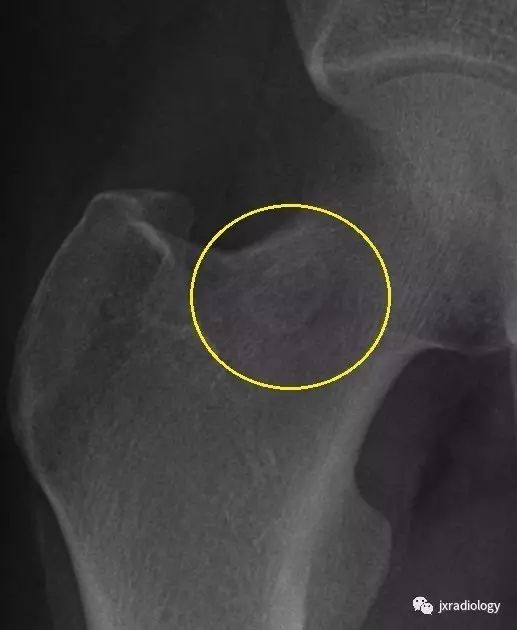

临床表现:股骨颈疝窝是发生于股骨头基底和股骨颈近端的一种较为少见的良性病变,发病率约 4%~5%,好发于中老年人,临床多无明显症状,常因其他病变检查时偶然发现。多位于股骨头基底和股骨颈前外侧 皮质下,可呈圆形或卵圆形。

影像表现:X 线平片上表现为伴有清晰薄层硬化缘的环形(囊状)透亮区,CT 上表现为圆形 或类圆形的皮质下局灶性骨质缺损,周围见薄层硬化带环绕,边缘锐利,部分较大病灶在病灶层面或上下相邻、层面上前方显示皮质与病灶相通的局部裂隙样缺损病灶,最大径线通常小于 10 mm;MRI 示病灶在 T1WI 上呈低信号,在 T2WI 上呈均匀或不均匀高信号。

鉴别诊断:X 线平片对股骨颈疝窝具有初步诊断价值;依据典型的CT和/或MRI影像学表现,对股骨颈疝窝多可以作出准确的诊断。需要与骨内的腱鞘囊肿相鉴别:是一相邻关节的囊性病变,内衬滑膜细胞并含有粘液样物质,有时液体内蛋白质较高在T1W 上信号趋向升高。